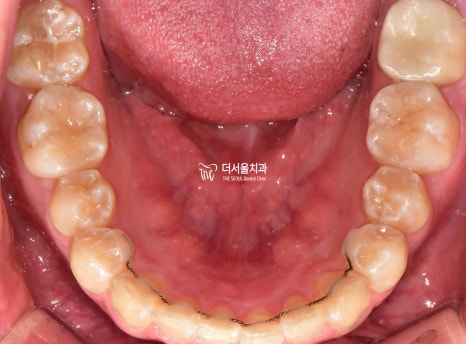

구강 사진을 보면

아랫니는 치열이 고르지 못한 것을 알 수 있었습니다.

전체적으로

문제점을 종합해 보면

2급 부정교합과 과개 교합을 나타내고 있었습니다.

상하악 치열궁 확장

하악 전치의 합입 및 이동을 하기 위해

인비절라인 후

구내 사진을 보여드리겠습니다

고르지 못했던 치열도

바르게 개선되면서 ‘U’ Shape를 나타냈으며

안쪽 면에 설측 유지 장치를 붙여드리게 되었습니다.

* 치아교정 전

#37번 큰 어금니에 충치가 있던 관계로

인비절라인을 마무리하면서

신경치료 및 크라운을 씌워드렸습니다.*